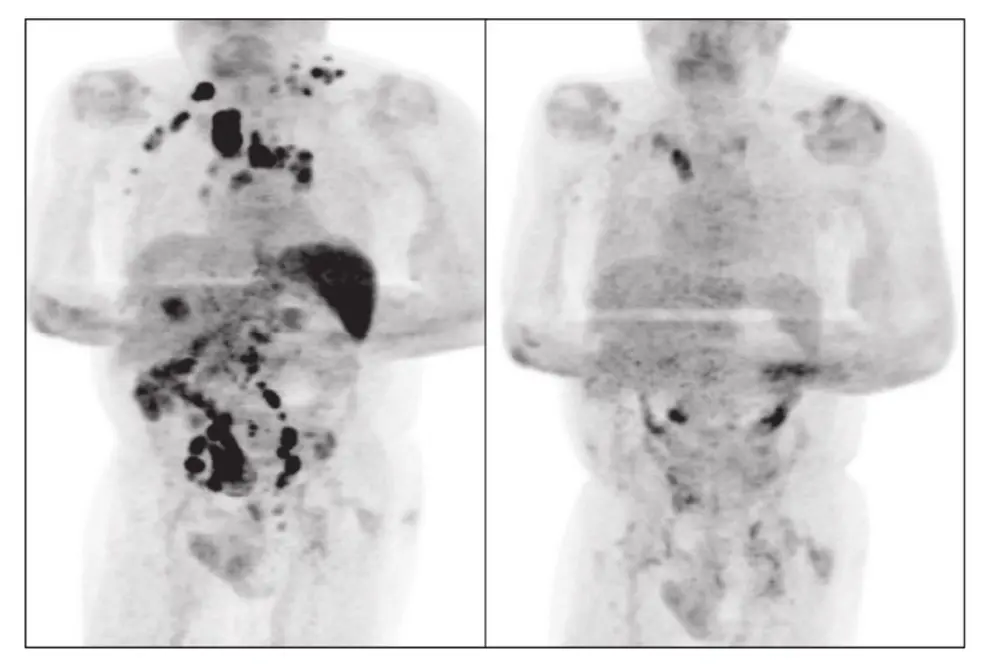

Legenda: O estudo de caso da remissão do câncer foi publicado no periódico especializado British Journal of Haematology

Foto: Reprodução/British Journal of Haematology

A rara remissão do linfoma de Hodgkin em um paciente britânico de 61 anos após ele ter sido infectado pela Covid-19 pode ser significativo para o estudo de novas terapias voltadas ao tratamento do câncer. É o que afirmam dois especialistas ouvidos pelo Diário do Nordeste.

Os autores de um artigo publicado no periódico especializado "British Journal of Haematology" sobre o assunto, Sarah Challenor e David Tucker, reforçam uma hipótese de que a infecção pelo Sars CoV-2 tenha desencadeado uma resposta imune contra o tumor, como já descrito em outras infecções em relação com o câncer em questão.